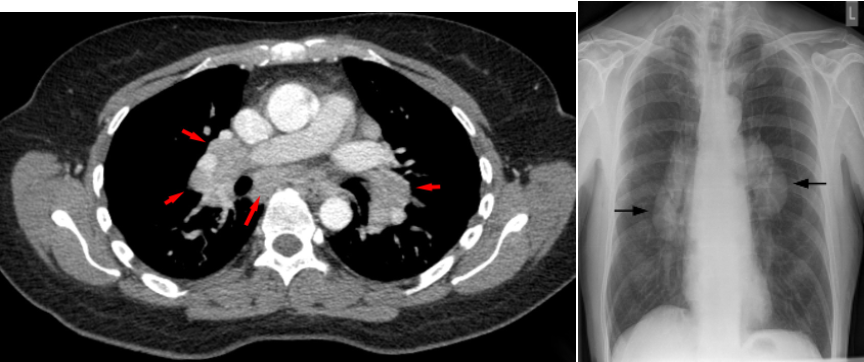

Bilateral enlargement of hilar nodes occurs in: triad

• Sarcoidosis-2 : The diagnosis is almost certain if the hilar enlargement is symmetrical and if the patient is asymptomatic, or has either erythema nodosum or iridocyclitis. Enlargement of the right paratracheal nodes is common. Lung changes are sometimes visible.